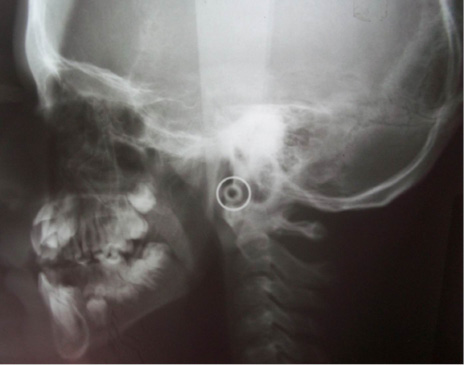

En el estudio imagenológico se observó en la radiografía de tórax, hipoplasia clavicular bilateral y tórax en forma de campana (Figura 2), en la radiografía panorámica se mostró la presencia de once dientes supernumerarios en el maxilar y nueve en la mandíbula (Figura 3), en la radiografía lateral cráneo se observó presencia de huesos wormianos landoideos (Figura 4); en la radiografía carpal se observó longitud simétrica de las falanges y sin alteraciones (Figura 5), de acuerdo con los hallazgos encontrados en el examen físico y la evaluación radiológica, se realizó la impresión diagnóstica de displasia cleidocraneal.

Figura 4. Radiografía lateral de cráneo en donde se observan huesos wormianos lamdoideos. Fuente: autores.